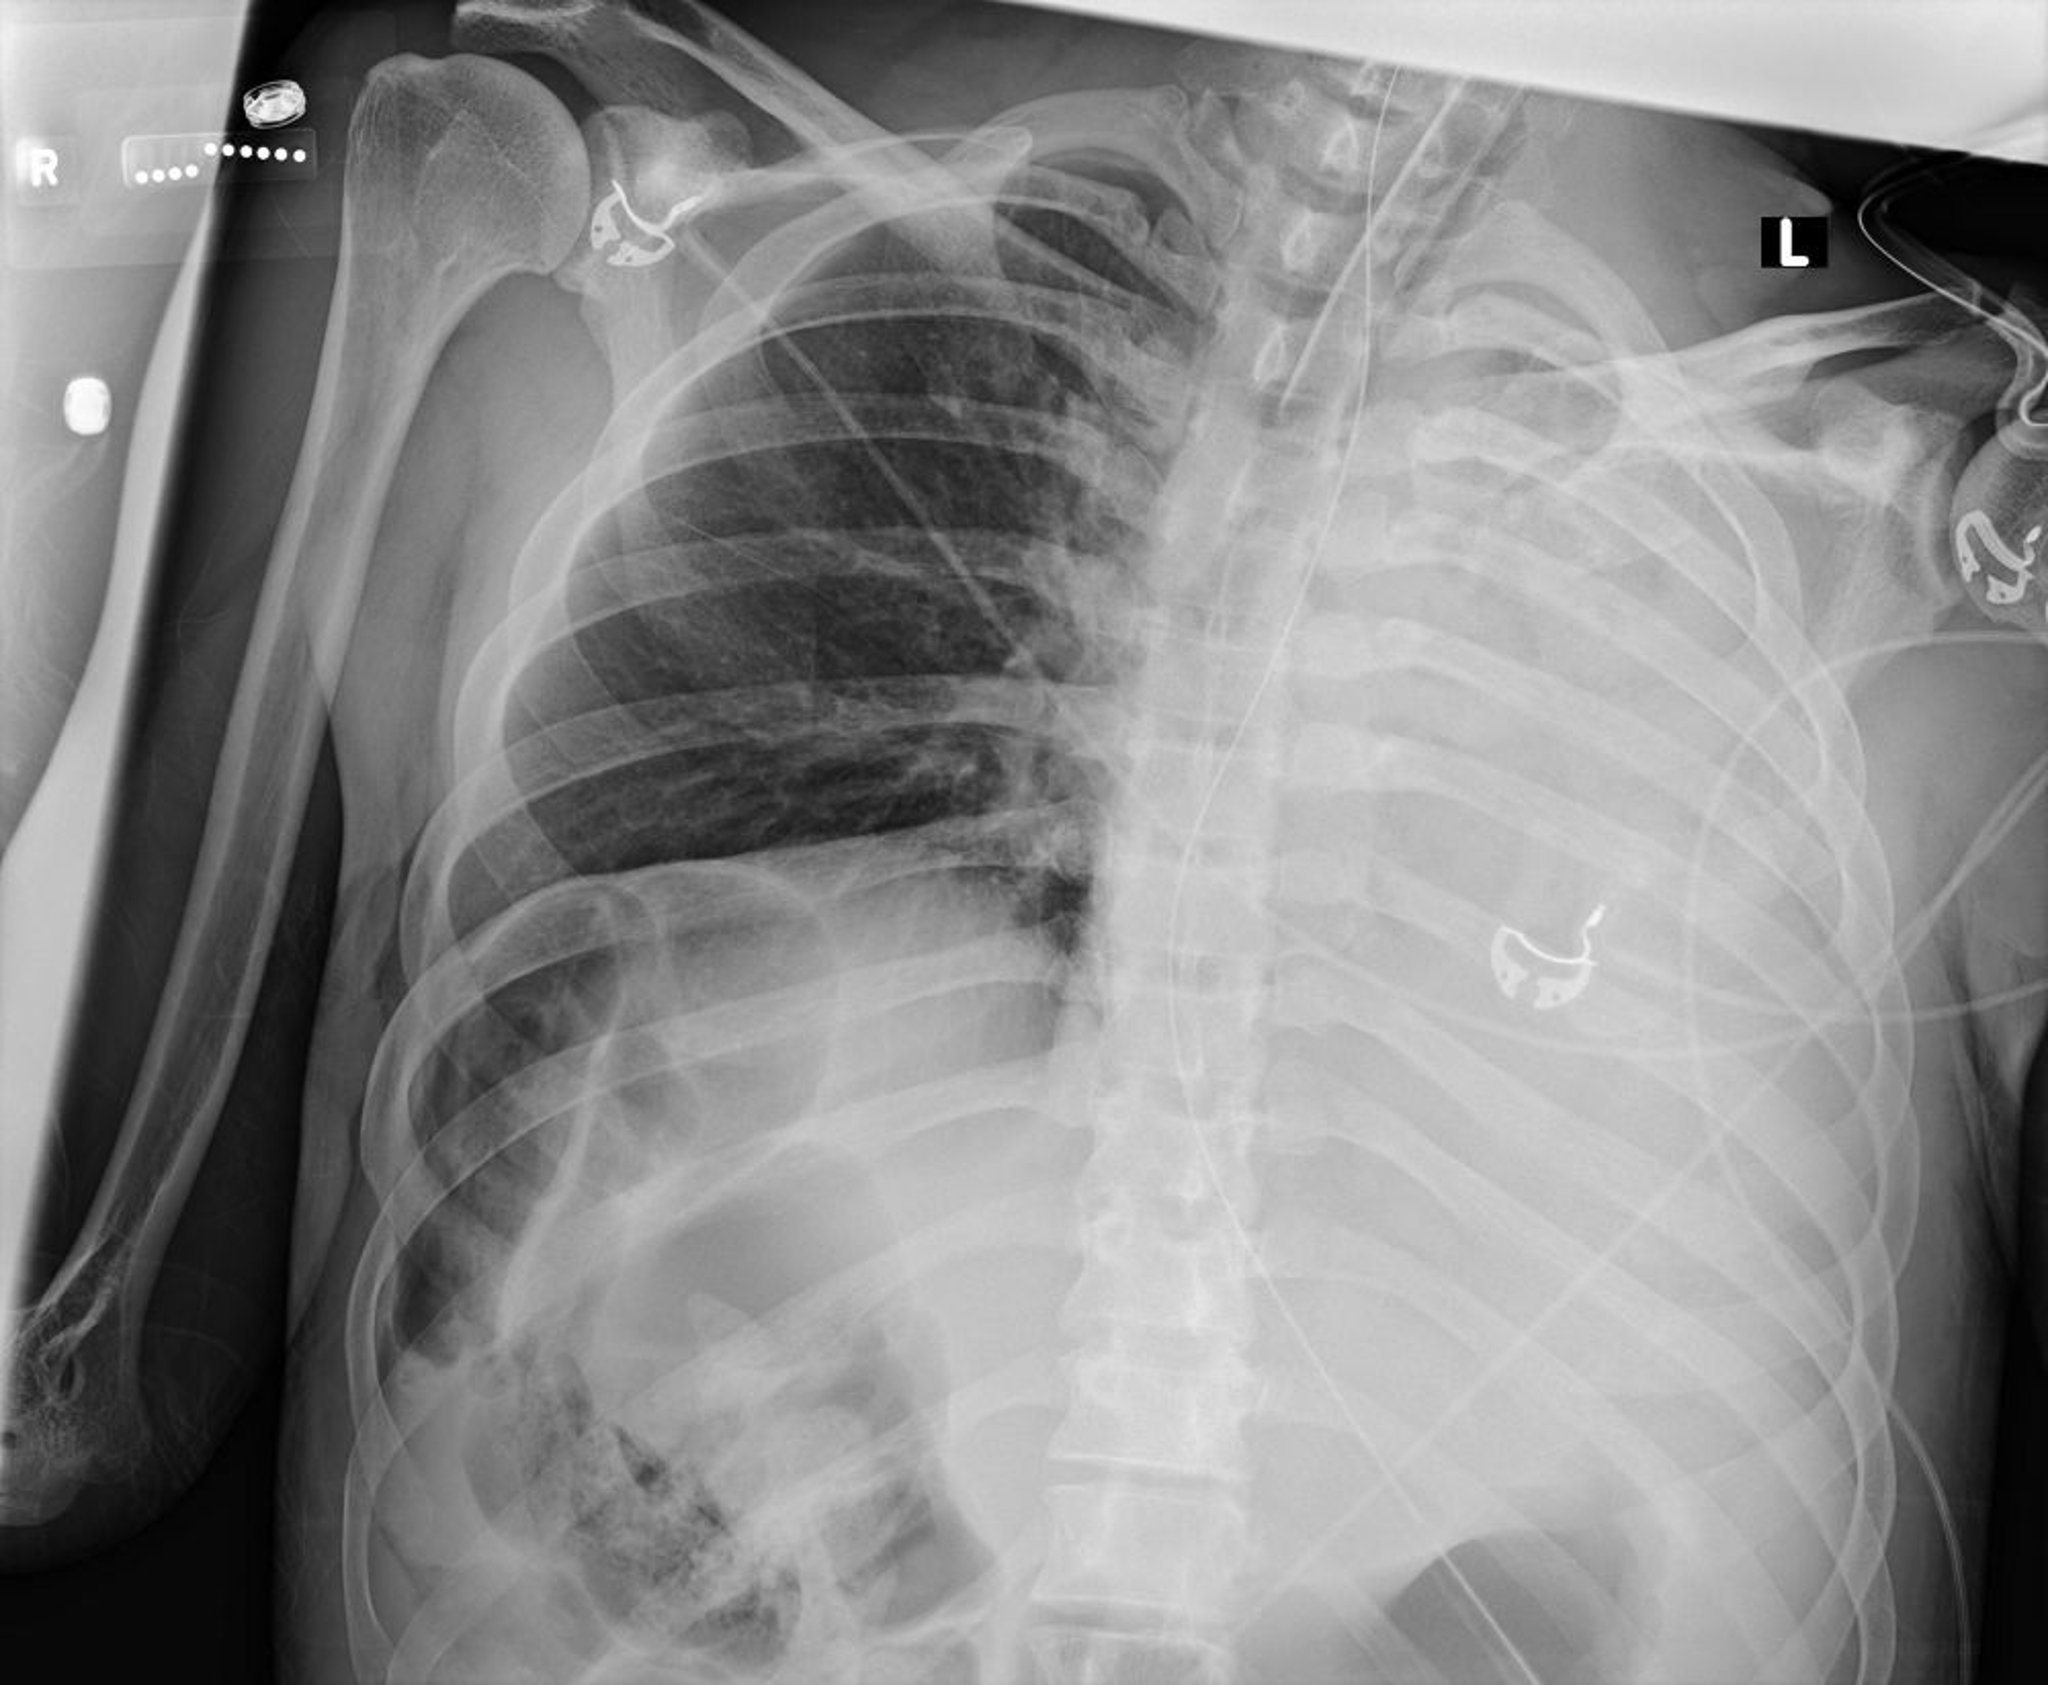

This chest radiograph shows collapse of all lobes of the left lung due to a mucus plug.

Courtesy of Alexander S. Niven, MD